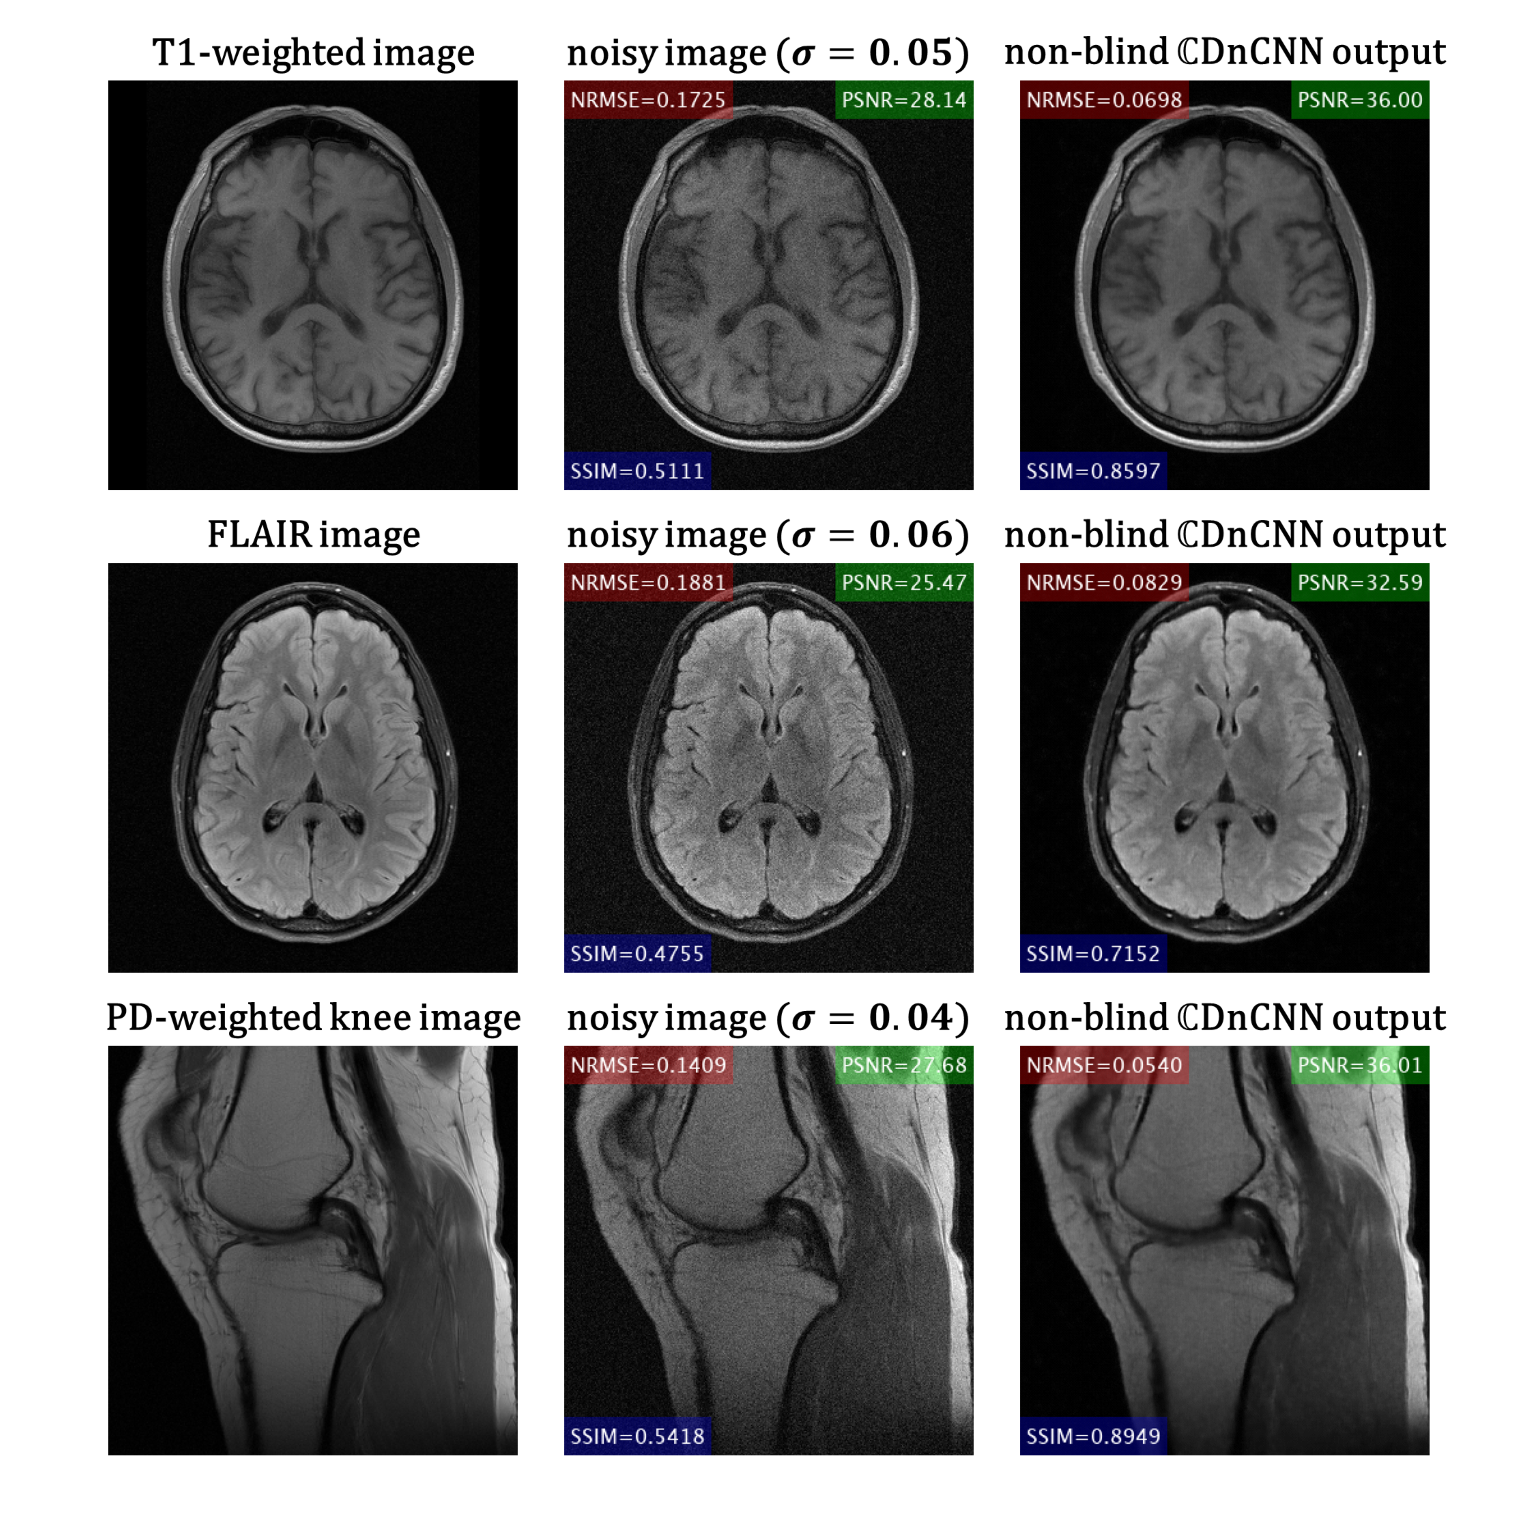

Figure 2A shows the quantitative evaluation results at different noise levels. The proposed non-blind $$$\mathbb{C}$$$DnCNN outperforms other methods with lower NRMSE, and higher PSNR and SSIM. Figure 2B shows representative slices from the testing dataset. The output of non-blind $$$\mathbb{C}$$$DnCNN shows reduced noise and less visual blurring compared to other methods. The computational cost for each method is summarized in Table 1. Figure 3 shows the network performance on SENSE reconstructed image. With scaled g-factor map as the noise level map, non-blind $$$\mathbb{C}$$$DnCNN successfully removed the spatially variant noise, while other methods failed at the center regions with large g-factor. Figure 4 shows the network performance on testing data out of the training distribution. The network is able to denoise the images and shows good generalization capability.

Figure 4 Representative slices from the testing dataset out of the training distribution.